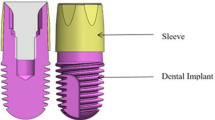

Study devices

All implants had the same surface and macroscopic design (C1 implants, MIS®); implants of the test group received an additional covalently bonded phosphonate layer that created a nanometer thin molecular nanolayer of monophosphonate molecules (Nano Bridging Molecules, Gland, Switzerland) (Fig. 2g).